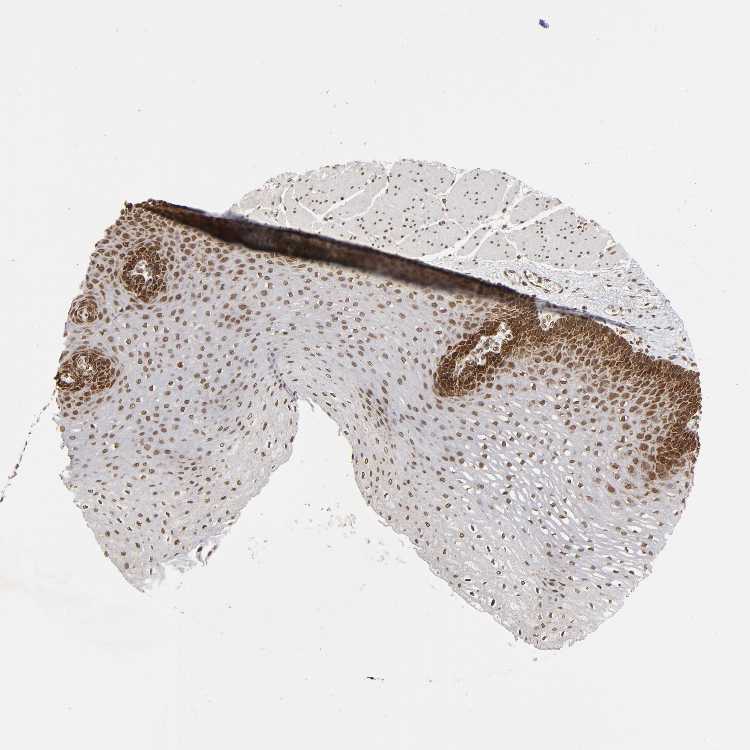

ESOPHAGUS - Antibody stainingi

Antibody staining in the annotated cell types in the current human tissue is reported as not detected, low, medium, or high, based on conventional immunohistochemistry profiling in selected tissues. This score is based on the combination of the staining intensity and fraction of stained cells.

Each image is clickable and will lead to virtual microscopy that enables deeper exploration of all samples and also displays staining intensity scores, fraction scores and subcellular localization as well as patient and tissue information for each sample.

Antibody HPA004021

Squamous epithelial cells Medium